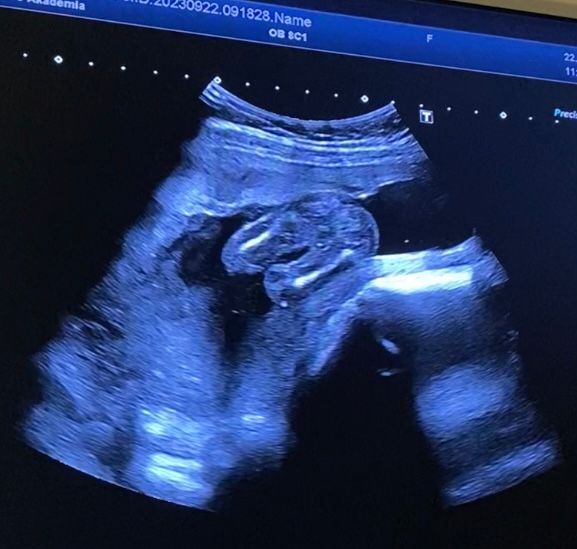

Пол 18 недель

Мальчик или девочка? Ошибка в поле на 17-18 неделях

В 16 недель на УЗИ было отлично видно яички и писюн, не додумалась сфоткать экран... Но там не спутать. Тут на девочку похоже

Может и прятаться конечно, но я с сыном в 17 недель ходила, там прям сильно видно. Я бы все таки на девочку подумала)

Девочка 100%, у меня на вашем сроке есть узи , там прям такое хозяйство видно 🤣

В 16 недель определили девочку 🥰 тут у вас 100% доченька 🌺